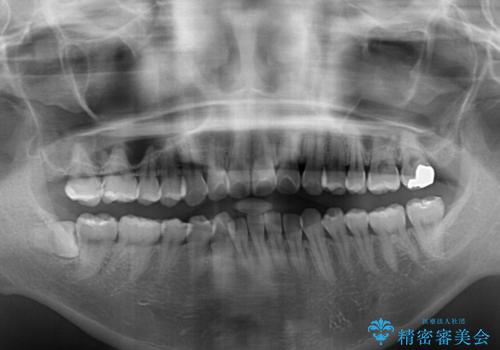

- 前方に傾斜した上下の前歯を気にして来院された患者様です。

唇の閉じにくさや横顔のシルエットが気になるような突出感ではなかったため、インビザラインを用いて、歯列の遠心移動とIPR(歯と歯の間を削る)により前歯の傾斜を改善していくこととしました。

スムーズに終了すると思われましたが、インビザライン矯正独特の奥歯が咬み合わない状態が続き、更には遠方へ転居されたこともあり、治療期間は長引いてしまいました。